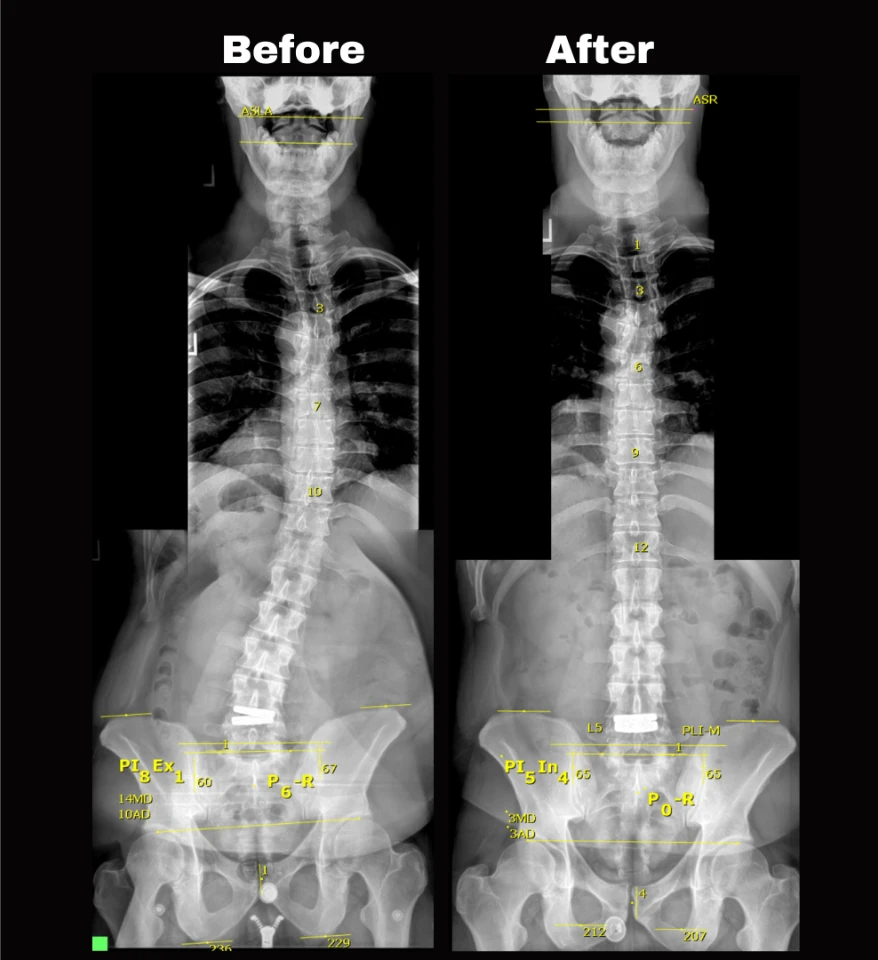

Chiropractors take x-rays to see the internal condition of the spine. X-rays also reveal if there are any underlying spinal disorders, such as arthritis of the spine, abnormal development, disc disorders, bone spurs, and spinal deterioration.

Having an x-ray taken before any adjustment helps chiropractors make a correct diagnosis. Combining x-rays with other exams will benefit the patient ultimately.